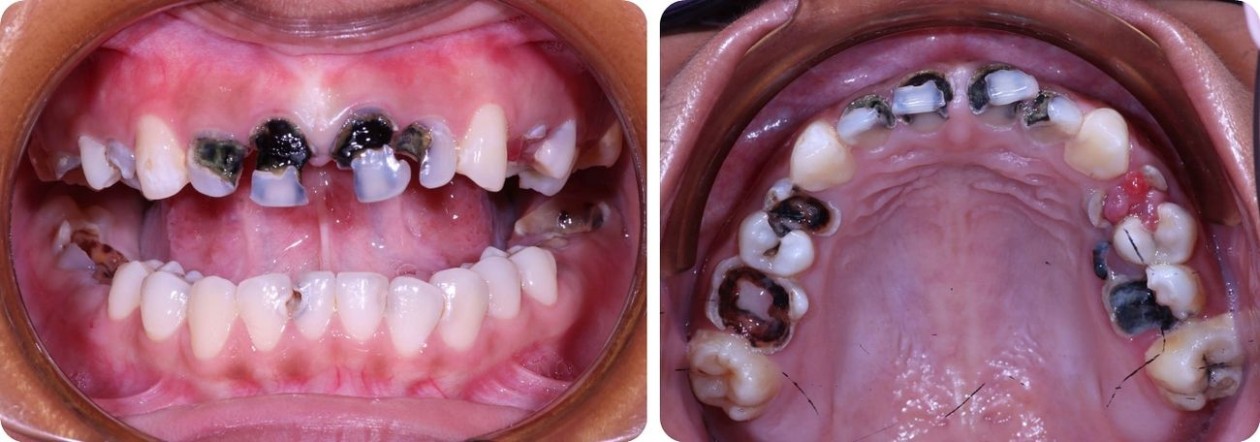

그 이유는 선천적으로 약해 모두 썩어버린 이빨 때문 입니다.

![]()

6,000$~10,000$나 필요한 밀리아의 치아를 치료하는 것은 꿈만같은 일입니다.

더 걱정인 것은 밀리아의 동생 메이메이도 밀리아처럼 치아가 썩어가고 있습니다.